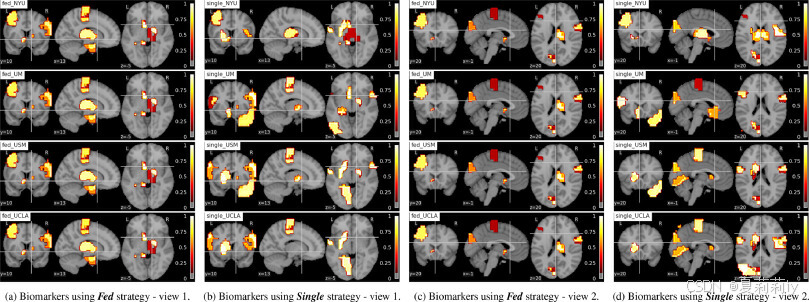

2.5.4. Evaluate model from interpretation perspective

(3)Neural patterns: Connectivity in the autistic brain

①They define "informativity" as functional representation difference between ASD and HC groups and "robustness" as the biomarker consistency of 4 sites

②They applied guided back-propagation method to detect the robust biomarkers of HC in Fed:

③ASD biomarker:

④Function correlation: